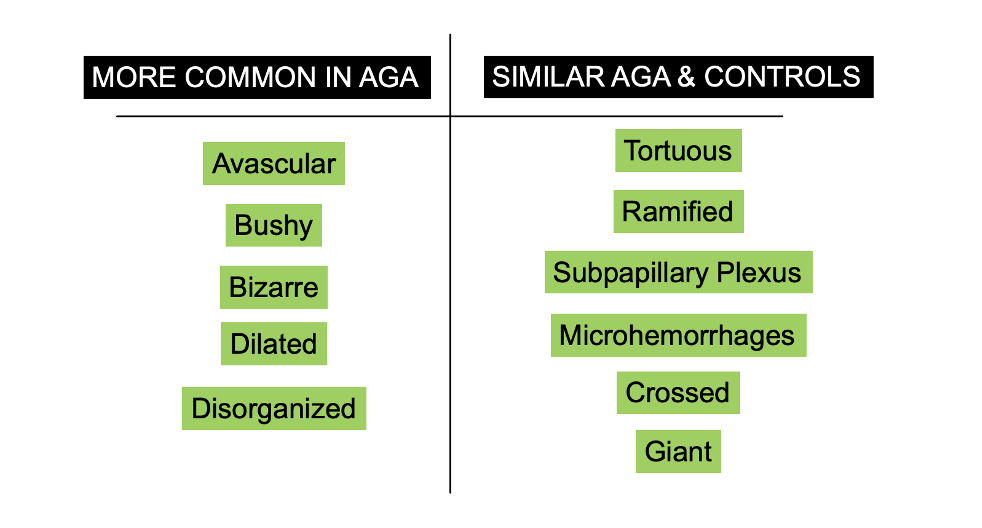

Avascular, Bushy, Bizarre and Disorganized and Dilated Capillaries more Common in AGA

Some capillary changes were more common in AGA than controls and some occurred with similar frequency. Specifically, the frequencies of avascular areas, dilated, bushy and bizarre capillaries and capillary disorganization were statistically higher in the androgenetic alopecia group than in healthy controls. Other abnormalities were similarly common in AGA and controls.

All in all, the authors propose that the frequency of capillary anomalies is higher in AGA than controls. This includes anomalies such as bushy, bizarre, dilated capillaries, capillary disorganization and avascular areas.